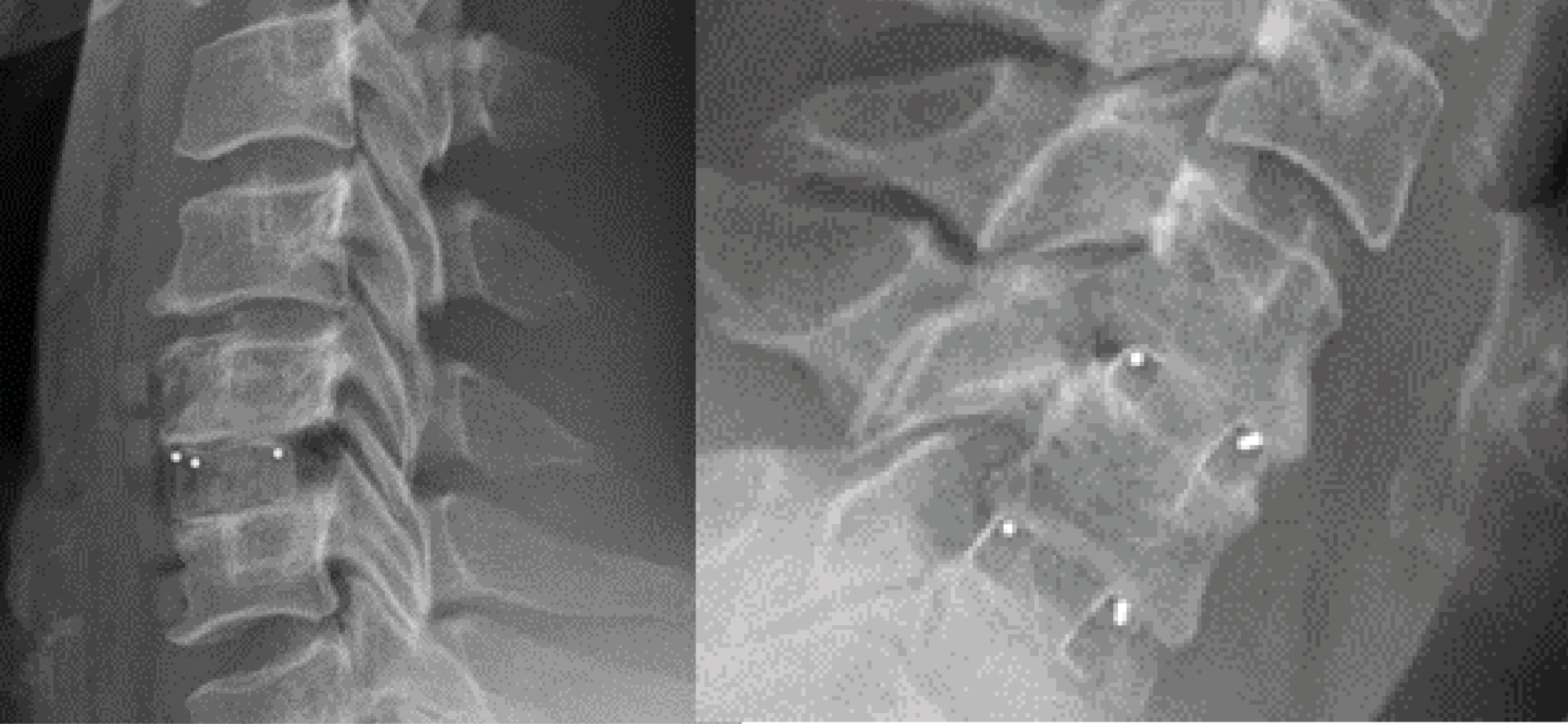

Figure 1 from Clinicoradiologic Assessment after Disc Cage Implantation Vertebral Disc Cage When the disk space has been cleared out, your surgeon will implant a metal, plastic, or bone spacer between. A spinal cage, also known as an interbody, is used in procedures that remove intervertebral discs from the spine. The spinal cage is placed in the disc space. The cage may occupy the entire disc space or just the front (anterior). Vertebral Disc Cage.